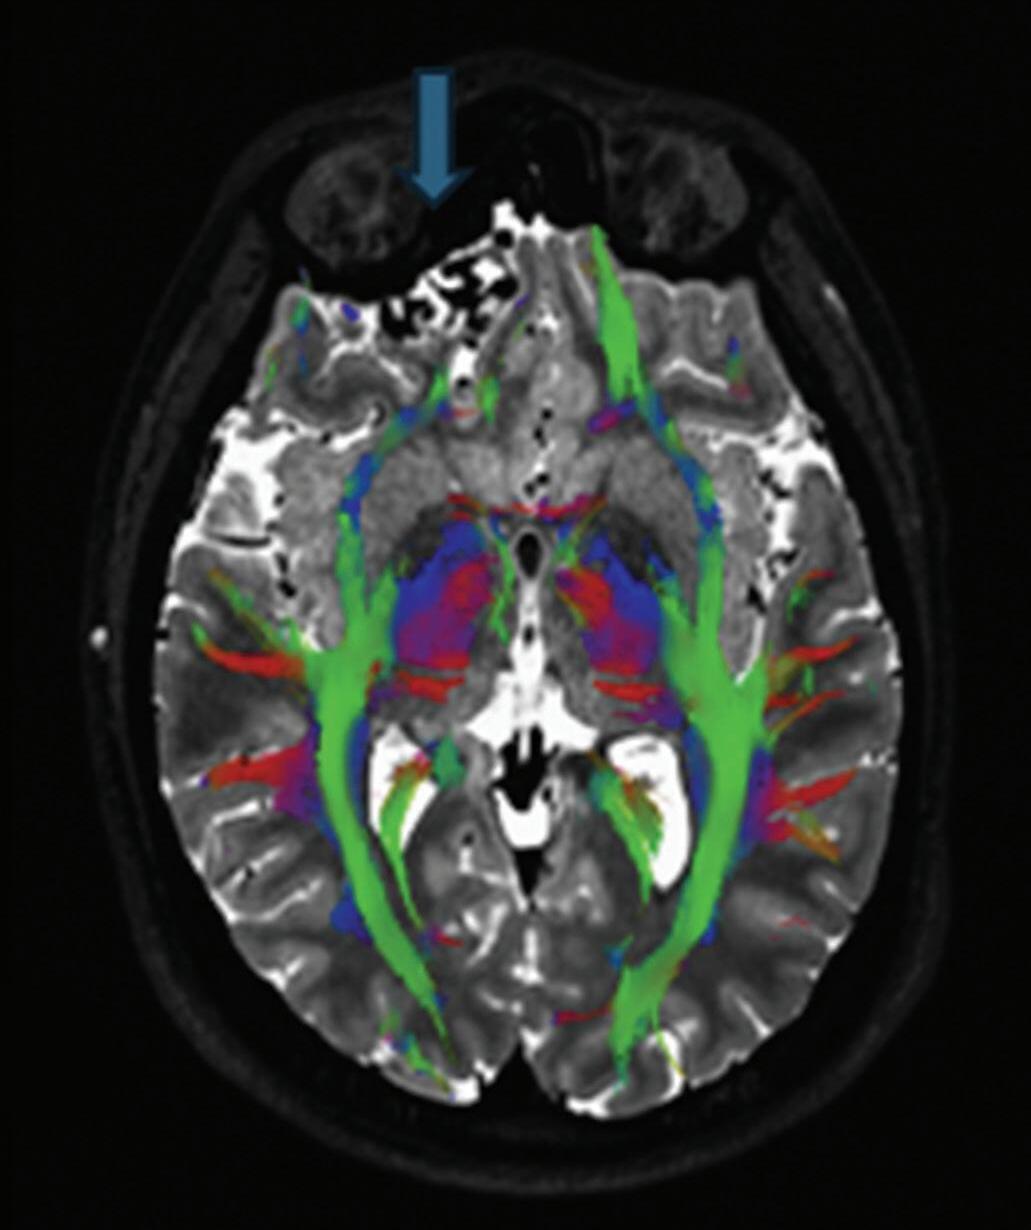

Fig. 1-8. (a-c) RNM T1 com contraste, cortes sagital (a), coronal (b) e axial (c) demonstrando MAV não rota com nidus localizado no lobo occipital à esquerda (setas longas). (d) Arteriografia digital cerebral com injeção de contraste via carótida direita (AP) mostrando a contribuição da carótida direita na irrigação da MAV contralateral. (e,f) Com injeção de contraste via carótida esquerda, em Perfil e AP respectivamente, observa-se nidus compacto nutrido por ramos da artéria cerebral média à esquerda e a veia de drenagem precoce se dirigindo para o seio sagital superior. Projeções em AP (g) e em perfil (h) demonstrando a contribuição do sistema vertebrobasilar por meio de ramos distais da artéria cerebral posterior à esquerda e drenagem para os seios sagital superior e sigmoide à esquerda (setas curtas).

Fig. 1-9. RNM T2 em cortes (a) axial e (b) sagital. (c,d) Tractografia axial – sagital, demonstrando a posição de uma MAV não rota localizada na superfície basal do lobo frontal, nos giros orbitários e reto à direita (setas longas). Arteriografia digital cerebral com injeção de contraste via carótida direita, (e) AP e (f) em perfil demonstrando MAV nutrida por ramos da artéria cerebral média e cerebral anterior direita e drenagem para o seio sagital superior (seta curta).